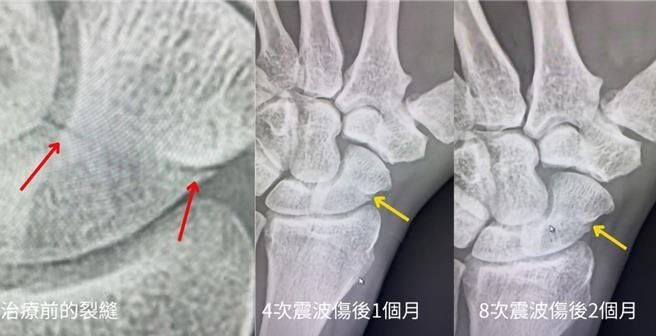

高雄一名47岁吊车驾驶,日前因右手舟状骨骨折,日夜抽痛难耐,为了不影响到工作,他向骨科医师寻求不打石膏、不做手术的治疗方式,活力得中山脊椎外科医师李松青接获此案,建议该患者戴上轻度护腕,并以聚焦式震波治疗,不仅能让患者继续工作,伤后2个月完全不疼痛,骨折也几乎癒合。

李松青指出,这名吊车驾驶是因为不小心跌倒导致右手骨折,且忍痛3天才就医,经检查发现该患者为舟状骨的中三分之一处骨折,自行癒合率低,但患者希望病情不影响开吊车工作,因此寻求不打石膏、不开刀的治疗方式。